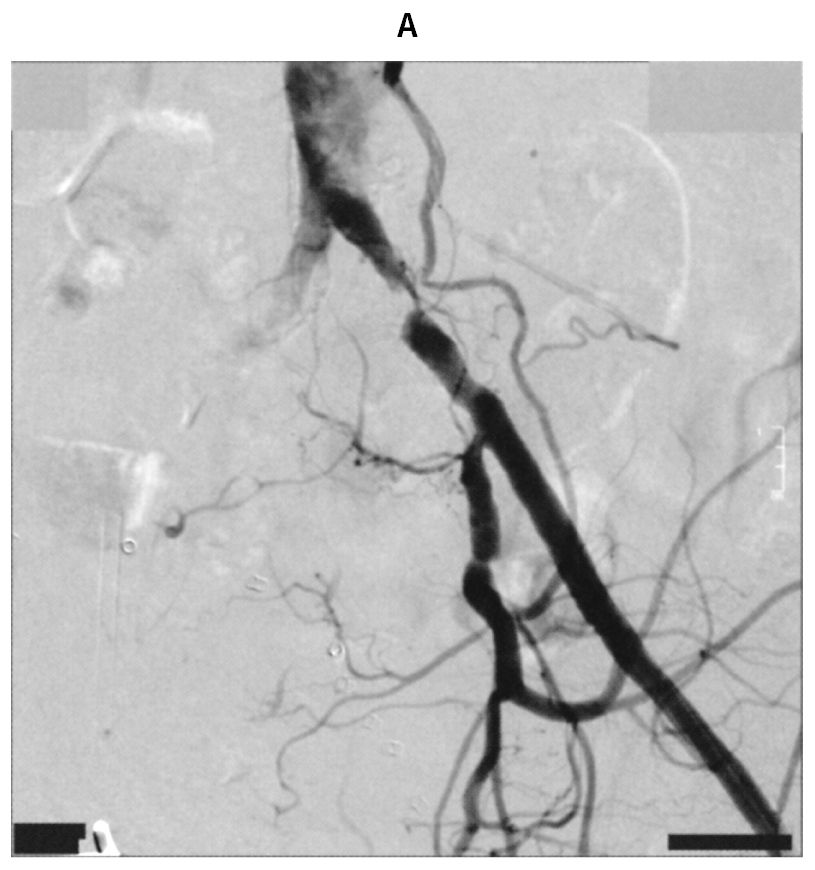

78歳の男性。歩行時の左下肢疼痛を主訴に来院した。4か月前から約300mの歩行で左下肢の痛みを自覚するようになり,立ち止まって休憩すると消失していた。最近痛みのため徐々に歩行可能距離が短くなった。60歳時から糖尿病と脂質異常症に対して定期的な投薬治療が行われている。喫煙は20歳から60歳まで20本/日。飲酒は機会飲酒。意識は清明。身長168cm,体重65kg。体温36.2℃。脈拍80/分,整。右上肢血圧160/90mmHg。呼吸数20/分。SpO2 96%(room air)。足関節上腕血圧比〈ABI〉は右側で0.96,左側で0.68であった。左大腿動脈から逆行性に造影した骨盤部の動脈造影の連続写真(A)(B)を下に示す。

研修医:「③左総腸骨動脈だと思います」